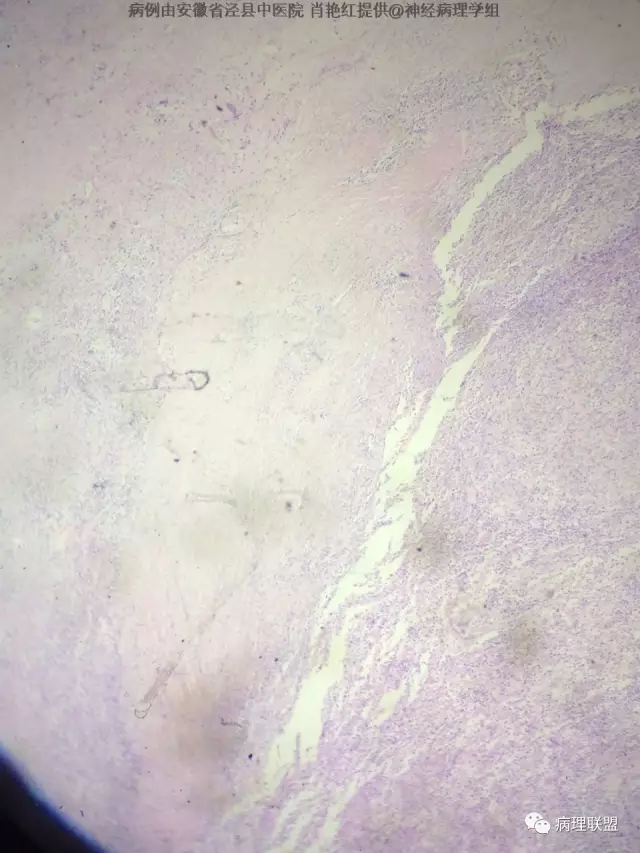

M/52 MRI示左侧小脑幕-(脑膜瘤-富于淋巴浆细胞型脑膜瘤?)

患者男,52岁,因突发头晕、恶心不适入院。头颅MRI示左侧小脑幕占位,血供分富,考虑脑膜瘤。巨检:灰白色肿物一枚,2*1.8*1.2cm,切面灰白、质中。(病例由安徽省泾县中医院 肖艳红提供,致谢!)